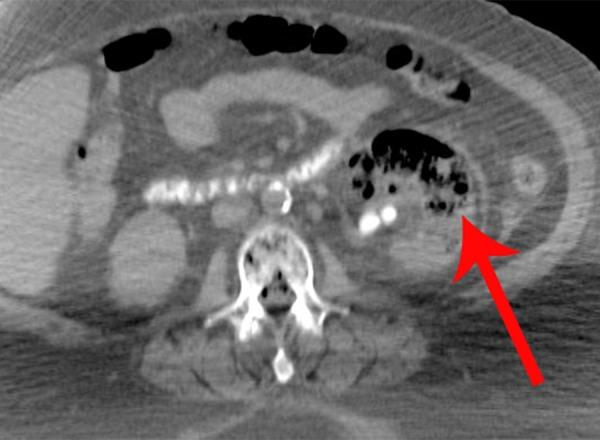

BACKGROUND Emphysematous osteomyelitis of the spine is characterized by intravertebral or intraosseous air. Emphysematous pyelonephritis (EP) is the infection of the renal parenchyma and perirenal tissues caused by gas forming microorganisms and thus is characterized by gas formation. Prompt diagnosis and initiation of necessary treatment is crucial, as both entities are associated with high mortality rates. CASE REPORT A 57-year-old female with uncontrolled hyperglycemia presented to the emergency department with history of sudden onset of weakness, nausea, vomiting and diarrhea for 3 days and with a fall on the same level the previous day. Laboratory examinations revealed leukocytosis, lymphopenia, thrombocytopenia, deteriorated renal function, and hyperglycemic hyperosmolar non-ketotic state. She was placed on aggressive intravenous hydration and insulin infusion pump. Due to the deterioration of her medical condition, she underwent abdominal and pelvic CT scanning that revealed emphysematous osteomyelitis of the spine and emphysematous pyelonephritis. Despite vigorous fluid resuscitation and systemic broad-spectrum antibiotic therapy, the patient's condition deteriorated further and eventually led to death within 48 h. CONCLUSIONS This case of fatal emphysematous osteomyelitis of the spine and EP serves as a significant reminder of those rare life-threatening entities, which affect patients with comorbidities, such as diabetes mellitus and other etiologies causing immunosuppression. The aim of the present case report is to highlight the importance and contribution of computed tomography in diagnosing these conditions and to emphasize the rare coexistence of these 2 emphysematous entities.

背景 脊柱气肿性骨髓炎的特征是椎体内或骨内出现气体。气肿性肾盂肾炎(EP)是由产气微生物引起的肾实质和肾周组织感染,其特征是形成气体。及时诊断并开始必要的治疗至关重要,因为这两种病症都与高死亡率相关。病例报告 一名57岁女性,血糖控制不佳,因突发乏力、恶心、呕吐和腹泻3天,且前一天在同一水平摔倒,就诊于急诊科。实验室检查显示白细胞增多、淋巴细胞减少、血小板减少、肾功能恶化以及高血糖高渗非酮症状态。她接受了积极的静脉补液和胰岛素输注泵治疗。由于病情恶化,她接受了腹部和盆腔CT扫描,结果显示脊柱气肿性骨髓炎和气肿性肾盂肾炎。尽管进行了积极的液体复苏和全身广谱抗生素治疗,但患者病情进一步恶化,最终在48小时内死亡。结论 这例致命的脊柱气肿性骨髓炎和EP病例显著提醒人们注意这些罕见的危及生命的病症,它们会影响患有合并症的患者,如糖尿病和其他导致免疫抑制的病因。本病例报告的目的是强调计算机断层扫描在诊断这些病症中的重要性和作用,并强调这两种气肿性病症罕见的共存情况。